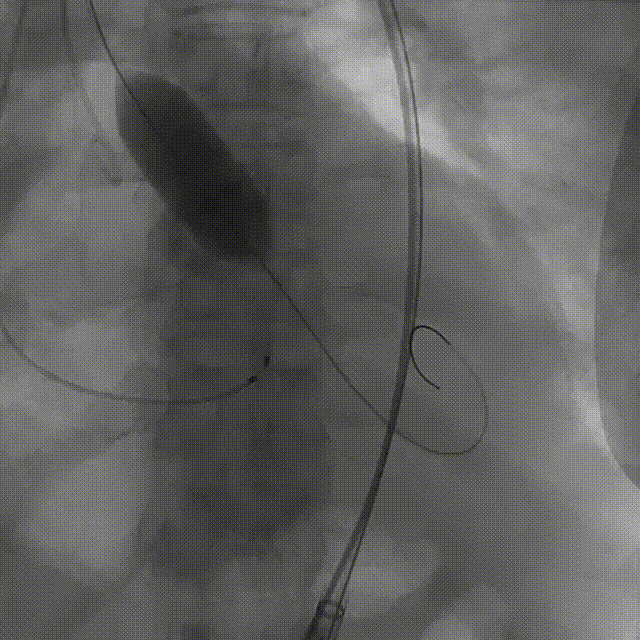

手术影像:

左冠造影灌注良好

右冠造影灌注良好

主动脉根部造影,狭窄伴反流

导丝顺利跨瓣

23mm球囊预扩无腰征,微量漏

输送器柔顺过弓、跨瓣

瓣膜开始零位定位

瓣膜逐步释放到工作位

工作位造影位置良好

瓣膜逐个脱钩

完全释放后造影,膨胀不良,有漏

25mm球囊后扩

后扩后瓣膜形态良好,造影基本无漏

外周血管造影检查良好